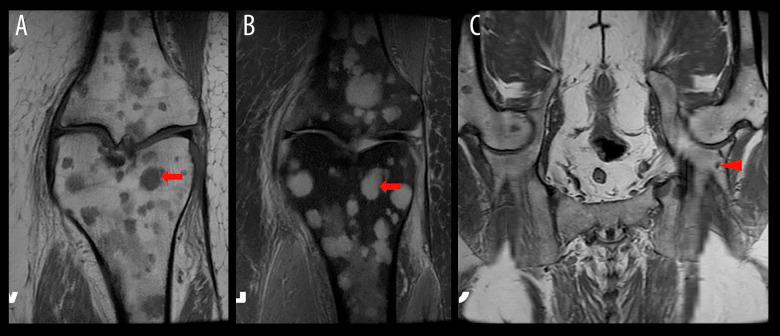

BACKGROUND Erdheim-Chester disease (ECD) is a rare neoplasm of histiocytes that is characterized by prominent involvement of the long bones. Approximately 1500 cases have been reported since the disease was first described in 1930. The imaging appearance of ECD can be highly variable given the numerous systems it can affect. In this case report we discuss a patient whose ECD was occult on multiple imaging modalities. CASE REPORT We report the case of a 60-year-old woman who presented with sub-acute left knee and calf pain that led to an MRI. She was found to have innumerable marrow-replacing lesions in the axial and appendicular skeleton visualized on the initial MRI, as well as on an ¹⁸F-FDG PET/CT scan. The patient did not have extraosseous abnormal uptake on the PET/CT. Subsequently, a lesion from the left iliac bone was histologically confirmed as ECD on the basis of positive staining for CD68 and CD163 and negative staining for CD1a. Osseous lesions in ECD have a distinct imaging appearance and are typically detected by radiography and bone scintigraphy, among other modalities; however, the lesions in this case were unexpectedly absent from those studies. CONCLUSIONS If there is a high degree of suspicion for ECD, 18F-FDG PET/CT and/or MRI may be necessary for adequate visualization of bone lesions, given that those lesions can have an infiltrative nature that may be difficult to image with other anatomic imaging modalities. Use of 18F-FDG PET/CT and/or MRI may also lead to adequate guidance of confirmatory biopsy.

我们报告了一位 60 岁女性的病例,她因亚急性左膝和小腿疼痛就诊,导致 MRI 检查。最初的 MRI 以及¹⁸F-FDG PET/CT 扫描显示,她的轴骨和附肢骨骼中存在无数骨髓替代病变。PET/CT 上患者没有骨外异常摄取。随后,根据 CD68 和 CD163 阳性染色以及 CD1a 阴性染色,从左髂骨病变活检组织学证实为 ECD。ECD 的骨病变具有独特的影像学表现,通常通过 X 线摄影和骨闪烁显像等其他方式检测到;然而,该病例中的这些病变却出乎意料地没有出现在这些研究中。